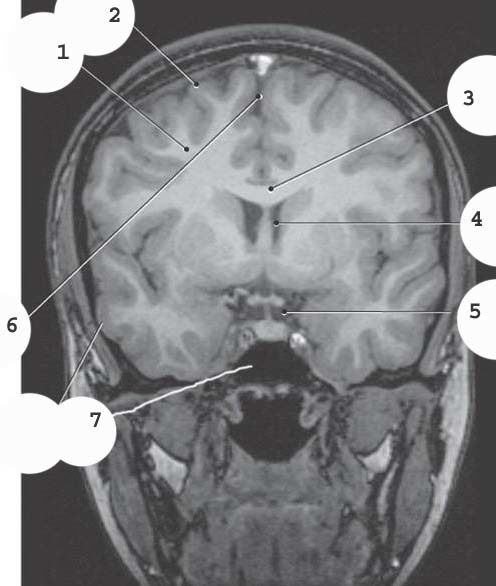

White matter

2

4

lateral ventricle

5

suprasellar cistern

6

Longitudinal fissure

7

sphenoid sinus

1

Superior Sagittal sinus